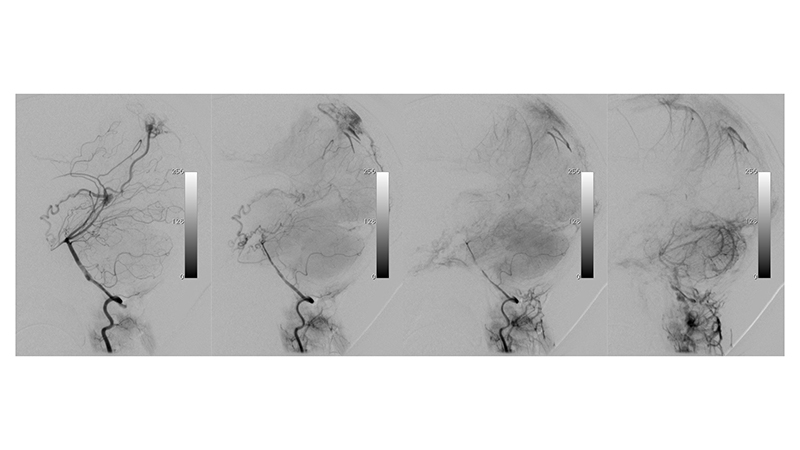

- Προσθιοπίσθια λήψη κατά την έγχυση στην αριστερή σπονδυλική αρτηρία. Ελέγχονται πολλαπλές μικροφίστουλες στο τοίχωμα της φλέβας του Γαληνού και μικρές αρτηριοφλεβώδεις επικοινωνίες στην χοριοειδή σχισμή (μικτού τύπου, τοιχωματικού και χοριοειδούς). Αρδεύονται από υποεπενδυματικούς τροφοφόρους κλάδους, εκ του Ρ1 τμήματος των οπισθίων εγκεφαλικών αρτηριών αμφοτερόπλευρα κυρίως δεξιά, που πορευόμενοι στο πλάγιο τοίχωμα της 3ης κοιλίας εκατέρωθεν, συναντούν την χοριοειδή σχισμή και εκείθεν αρδεύουν την αρτηριοφλεβώδη επικοινωνία (μαύρα βέλη). Επίσης συμμετέχουν οπισθιοπλάγιοι έσω χοριοειδείς (διακεκομμένο κόκκινο βέλος) και οπισθιοπλάγιοι έξω χοριοειδείς κλάδοι (κόκκινο βέλος) από το Ρ2 και Ρ3 τμήματα των οπισθίων εγκεφαλικών αρτηριών αμφοτερόπλευρα, που δια της χοριοειδούς σχισμής καταλήγουν στο οπίσθιο τοίχωμα της φλέβας του Γαληνού. Διακρίνεται επίσης η απόφραξη των εγκαρσίων κόλπων και η αναστροφή της ροής προς το εγκεφαλικό φλεβικό δίκτυο με συμφόρηση των εγκεφαλικών φλεβών.

- Πλαγία λήψη κατά την έγχυση στην αριστερή σπονδυλική αρτηρία. Τροφοφόροι θαλαμοδιατιτραίνοντες (διακεκομμένο μαύρο βέλος) και υποεπενδυματικοί κλάδοι (διακεκομμένο μπλέ βέλος), εκ της οπισθίας αναστομωτικής και του Ρ1 τμήματος των οπισθίων εγκεφαλικών αρτηριών, που πορευόμενοι στο πλάγιο τοίχωμα της 3ης κοιλίας εκατέρωθεν, συναντούν την χοριοειδή σχισμή και εκείθεν αρδεύουν την αρτηριοφλεβώδη επικοινωνία (μαύρα βέλη). Παρατηρείται αναστροφή της ροής στον άνω οβελιαίο κόλπο με φλοιώδη παλινδρόμηση προς τα εγκεφαλικά ημισφαίρια αμφοτερόπλευρα (κόκκινα βέλη). Οι εγκάρσιοι κόλποι αποφράσσονται, και μέσω των περιμεσεγκεφαλικών φλεβών παρατηρείται παροχέτευση προς το περιμυελικό φλεβικό δίκτυο του νωτιαίου μυελού (μπλέ βέλη) το οποίο παρουσιάζει εκσεσημασμένη συμφόρηση αλλά και διά του άνω λιθοειδούς κόλπου προς τον σηραγγώδη κόλπο (μαύρα βέλη).

- Αξονική τομογραφία με σκιαγραφικό και αγγειογραφία του σπονδυλοβασικού συστήματος σε πλάγια λήψη. Διακρίνεται κατιούσα φλεβική παροχέτευση προς το περιμυελικό φλεβικό δίκτυο του νωτιαίου μυελού (μπλέ βέλη) το οποίο παρουσιάζει εκσεσημασμένη συμφόρηση.